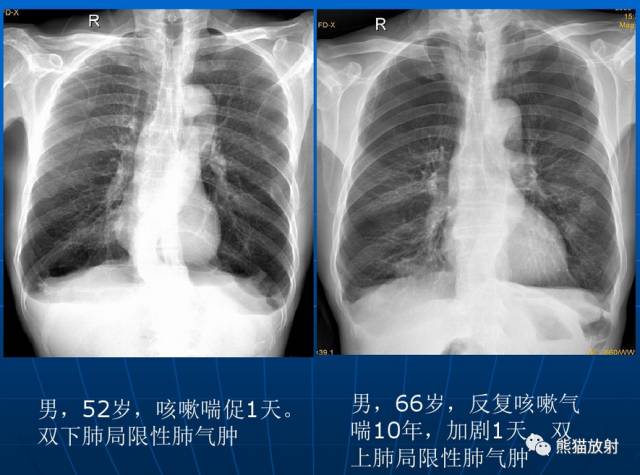

局限性阻塞性肺气肿是由于一个较大的支气管产生部分性阻塞所引起。该病可见于支气管内异物、小儿急性肺炎、早期支气管肿瘤和支气管慢性炎性狭窄包括结核等病史。

X线表现:在肺野内有局部的透亮度增高区域,其部位和范围取决于支气管部分阻塞的所在。至于有无胸廓、横膈等改变取决于病变的范围和部位。

| 局限性阻塞性肺气肿 |